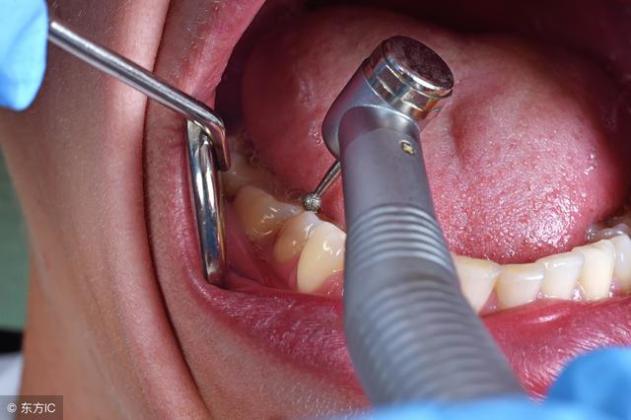

4. 医院就诊。如果太严重了,就要到医院马上就诊,必要的话,可以将智齿拔出。长智齿并不可怕,可怕的是我们的处理方式不对,从而加重了病情。开始发现智齿就应该更重视口腔的卫生,避免诱发一系列牙病,当感觉智齿出现异常时就应该去医院就诊,切勿错过最佳的治疗时间。